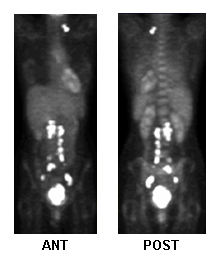

tomografia por emissão de pósitrons (PET) do corpo inteiro

Usado para avaliar a disseminação local/metastática e auxiliar o planejamento do tratamento.[98][103]

Detecção de recidiva: sensibilidade de 80%, especificidade de 100%.[105][Figure caption and citation for the preceding image starts]: Tomografia por emissão de pósitrons (PET) com fluordesoxiglucose para planejamento de tratamento, atividade metastáticaDo acervo de Neil S. Horowitz, MD; usado com permissão [Citation ends].

Resultado

pode revelar aumento da atividade metabólica nas áreas de envolvimento